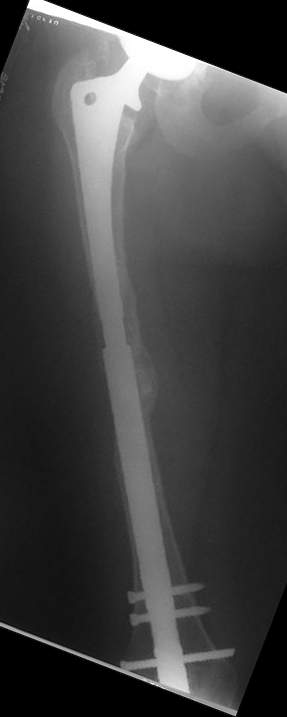

Female, rheumatoid, THA in 2003, car accident in 2006, failed plating. Nailing in Oct 2007. The nail is solid with hollow proximal part where the stem is docked. Last images are in 1 year after

nailing.

Спасибо за обсуждение. После нескольких дней тракции аппаратом сделали. Попытка закрытой репозиции не удалась из-за смещения по ширине, мешали фрагменты цемента. После их удаления репозиция получилась. Еще убрали немного цемента с ножки по латерльной стороне, чтобы обнажить 40-50 мм ее дистальной части, для плотной посадки гвоздя. Дальнейшее введение гвоздя было несложным. Протез показался нам стабильным в проксимальной части как латерально, так и медиально. Картинки в приложении.

THX for the discussion. After few days of traction by ex-fix the surgery was performed. An attempt of closed nailing was unsuccesful because of fragment translation, which was blocked by cement fragments. After removal of broken cement pieces reduction was reached "automagically". Also some cement from lateral part was removed by

chisel to expose distal 40-50 mm of the stem to allow tight fit of the nail. Further fixation by the nail was pretty easy and straightforward. Images attached. The stem looked stable in its proximal part both laterally and medially. Comments/critics are welcome.